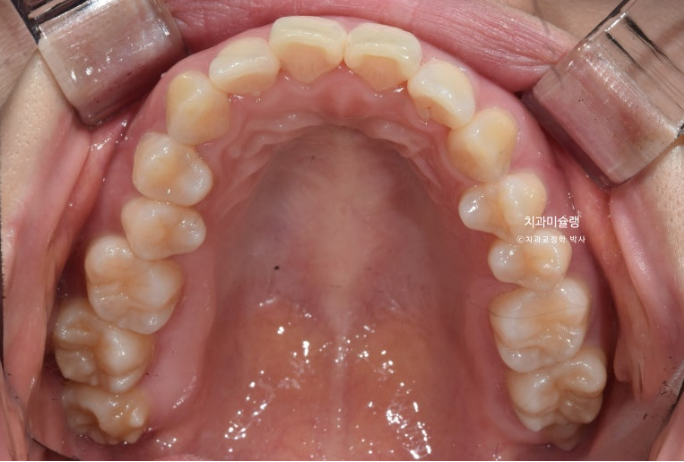

중심선은 잘 맞으며 과개교합을 개선하기 위한 교정용 나사를 심고 진행했습니다.

상악 발치공간이 양측으로 각각 1mm씩 남은 상태라서 재제작에 들어갔습니다.

발치공간이 소량 남은 것 이외에 치아 뿌리 평행도도 양호하고 어금니 쓰러짐도 없이 잘 진행된 편이라 이때까지만 해도 토탈 치료기간이 토탈 2년을 넘지 않을 것으로 예상했습니다.